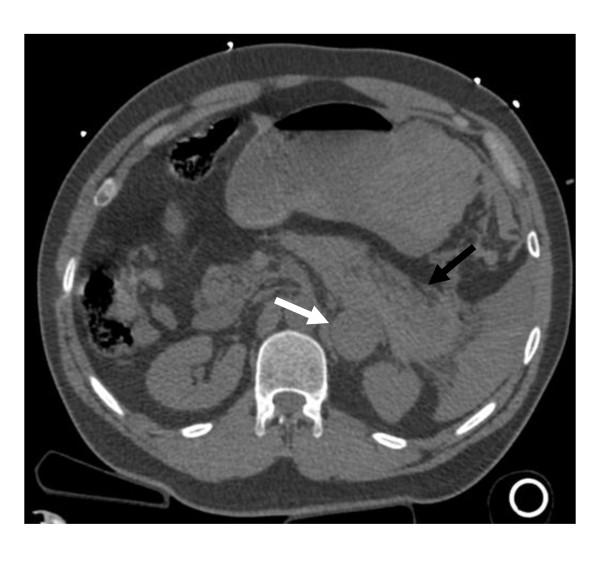

自发性肾上腺嗜铬细胞瘤破裂并发腹腔内出血和休克。

Spontaneous adrenal pheochromocytoma rupture complicated by intraperitoneal hemorrhage and shock.

MEN2A is a hereditary syndrome characterized by medullary thyroid carcinoma, hyperparathyroidism, and pheochromocytoma. Classically patients with a pheochromocytoma initially present with the triad of paroxysmal headaches, palpitations, and diaphoresis accompanied by marked hypertension. However, although reported as a rare presentation, spontaneous hemorrhage within a pheochromocytoma can present as an abdominal catastrophe. Unrecognized, this transformation can rapidly result in death. We report the only documented case of a thirty eight year old gentleman with MEN2A who presented to a community hospital with hemorrhagic shock and peritonitis secondary to an unrecognized hemorrhagic pheochromocytoma. The clinical course is notable for an inability to localize the source of hemorrhage during an initial damage control laparotomy that stabilized the patient sufficiently to allow emergent transfer to our facility, re-exploration for continued hemorrhage and abdominal compartment syndrome, and ultimately angiographic embolization of the left adrenal artery for control of the bleeding. Following recovery from his critical illness and appropriate medical management for pheochromocytoma, he returned for interval bilateral adrenal gland resection, from which his recovery was unremarkable. Our review of the literature highlights the high mortality associated with the undertaking of an operative intervention in the face of an unrecognized functional pheochromocytoma. This reinforces the need for maintaining a high index of suspicion for pheochromocytoma in similar cases. Our case also demonstrates the need for a mutimodal treatment approach that will often be required in these cases.

MEN2A 是一种遗传性综合征,其特征为甲状腺髓样癌、甲状旁腺功能亢进和嗜铬细胞瘤。经典的嗜铬细胞瘤患者最初表现为阵发性头痛、心悸和出汗三联征,并伴有明显的高血压。然而,尽管报告为罕见表现,但嗜铬细胞瘤内的自发性出血可表现为腹部灾难。如果未被识别,这种转变可能会迅速导致死亡。我们报告了唯一一例 MEN2A 的 38 岁男性患者,他因未被识别的出血性嗜铬细胞瘤导致失血性休克和腹膜炎而就诊于社区医院。临床过程的特点是在最初的损伤控制性剖腹术中无法定位出血源,这足以使患者稳定,以便紧急转至我们的机构,再次探查持续出血和腹腔间隔室综合征,并最终进行左肾上腺动脉血管造影栓塞以控制出血。在从危重病中康复并对嗜铬细胞瘤进行适当的药物治疗后,他接受了双侧肾上腺切除术,术后恢复良好。我们对文献的回顾强调了在面对未被识别的功能性嗜铬细胞瘤时进行手术干预的高死亡率。这再次强调了在类似情况下保持对嗜铬细胞瘤高度怀疑的必要性。我们的病例还表明,在这些情况下通常需要采用多模式治疗方法。